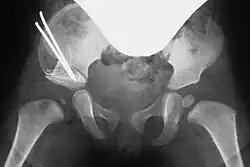

Entsprechend dem so entstandenen Spalt wird bei beiden Vorgehensweisen ein passender Knochenkeil (Spenderknochen/Knochenbank, siehe unten) zurechtgesägt und unter Röntgenkontrolle in den Spalt eingestößelt. Der Keil kann wenn nötig mit einem Osteosynthese-Draht (auch Kirschner-Draht genannt) fixiert werden. Bei einem geübten Operateur dauert diese Operation in etwa fünfundvierzig bis sechzig Minuten.[1][8]

Im Anschluss an die Operation wird ein entsprechender Beckenbeingips (modifizierter Fettweiss-Gips) oder eine Abduktions-Orthese angelegt, damit der Hüftkopf während der postoperativen Heilung zentral in der Pfanne steht. Die Narkose wird erst im Anschluss daran beendet.[4]

Ein postoperatives Versagen oder Einbrechen (Sintern) des Knochenkeils kann eine erneute Operation notwendig machen. Ebenso kann es passieren, dass der Knochenkeil nicht fest genug verankert wurde und er sich postoperativ aus dem Osteotomiespalt löst, was meistens zur Auflösung (Lyse) des Keils führt.[8] Durch den Beckenbeingips kann es zu Druckschäden oder Nervenreizungen kommen.